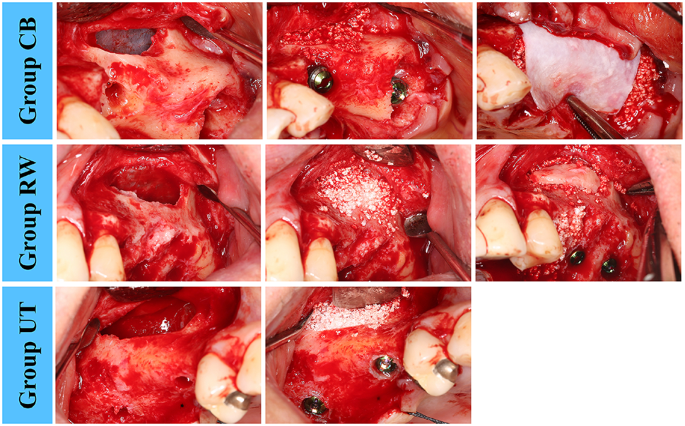

The following study groups were established based on the treatments applied to the bony access window:

Group CB (collagen barrier): covering the bony window with a collagen barrier.

Group RW (repositioned window): repositioning the bone fragment that was detached from the lateral wall of the sinus.

Group UT (untreated): leaving the window to heal without any treatment.

After bone grafting and implant placement, a cross-linked collagen barrier (Genoss Collagen Membrane, Genoss) was applied to the window and its nearby surrounding area in group CB, with the barrier extending 2–3 mm beyond the window margin. In group RW the detached bone fragment was repositioned, while no other treatment was performed in group UT. In case of bony deficiency (other than the sinus), guided bone regeneration was performed using the same bone substitute material and collagen barrier. The flaps were sutured for submerged healing using non-resorbable suture material (Fig. 3).